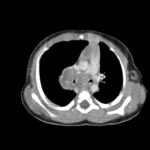

Infant tuberculosis (TB) is a rare but potentially deadly infection and difficult to diagnose, especially in infants who may present with non-specific symptoms. Here, we report a case of an United States-born term infant with community-acquired miliary TB and no confirmed TB exposure history. The patient initially presented with respiratory distress at seven weeks of life with chest radiograph showing a right lower lobe (RLL) infiltrate. After failing multiple courses of treatment for community-acquired pneumonia and developing growth faltering, the patient had imaging findings suggestive of TB infection with CNS involvement. The diagnosis of TB was confirmed by QuantiFERON and purified protein derivative (PPD). In infants who fail conventional treatment for bacterial pneumonia, the differential should be broadened to consider alternative etiologies. Additionally, brain imaging should be performed in cases of disseminated TB despite negative cerebrospinal fluid (CSF) studies since these patients are at high risk of central nervous system (CNS) involvement.